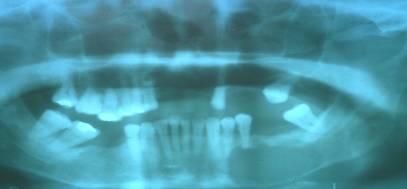

La radiografía panorámica revela imagen radiolúcida unilocular extendiéndose desde canino hasta el tercer molar. Fig. 3

Figura 3. Rx Panorámica